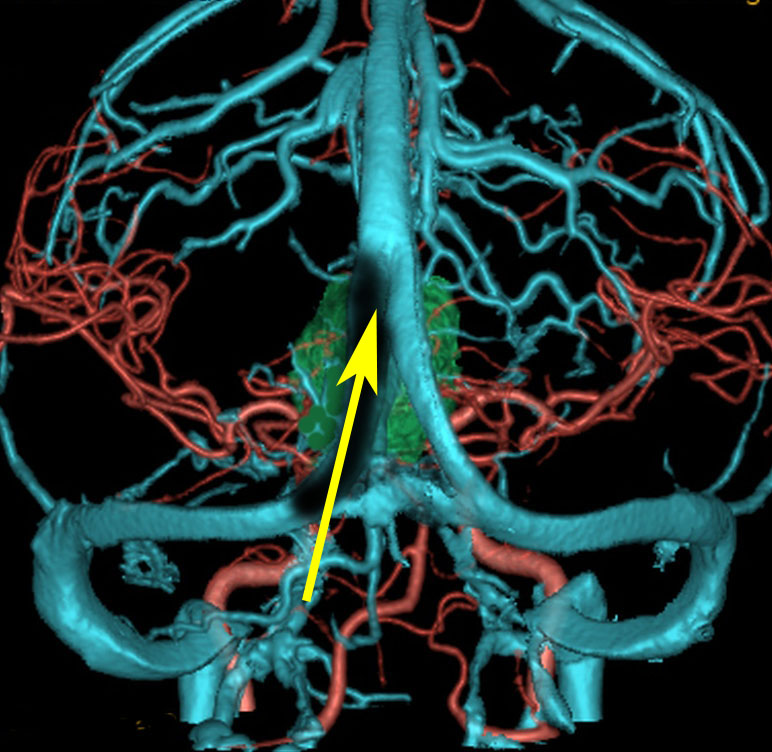

松果体腫瘍へのOTAのルートです。occipital transtentorial apporachというのは黄色の矢印に沿ってガレン大静脈の下に入る方法であり,そこから松果体部を通って第3脳室内へ直線的な視野が展開します。

一方,赤の矢印に沿ったルートは parieto-occipital transtentorial approachです。このルートでは内大脳静脈 internal cerebral veins を見ることがかなり難しいです。更に,第3脳室に入るためには脳梁膨大部 spleniumを切断する必用があります。ただし,小脳上部や第4脳室を見るときにはparietal寄りのルートを使います。

この2つのルートを混同している脳外科の先生はとても多いと思います。OTAとは,外後頭隆起を削除して,後頭極(後頭葉)を牽引して,テントの全長を切開しなければ遂行できない到達法であることを認識して下さい。